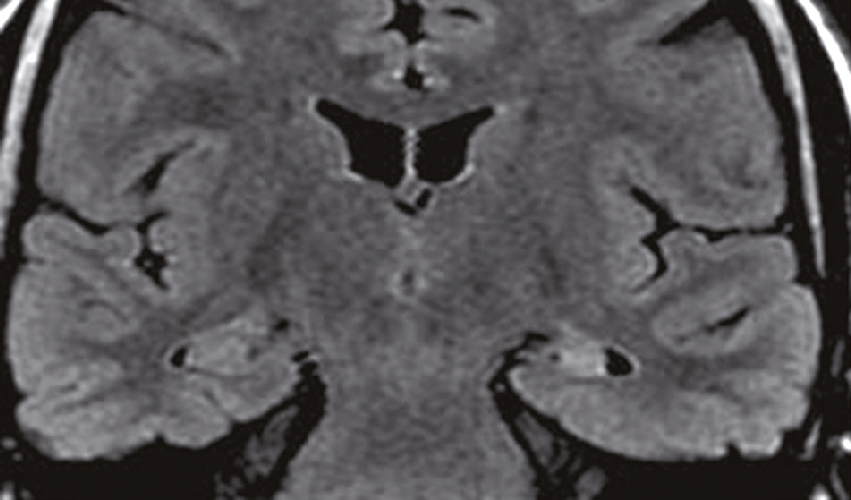

Une IRM encéphalique est réalisée (fig. 31.7). Sur cette planche, quels sont les éléments évocateurs du diagnostic de sclérose en plaques (SEP) ?

- A 585présence d’hypersignaux de la substance blanche

- B localisation surtout périventriculaire des hypersignaux

- C aspect arrondi des hypersignaux

- D présence de trous noirs

- E atrophie cérébrale marquée